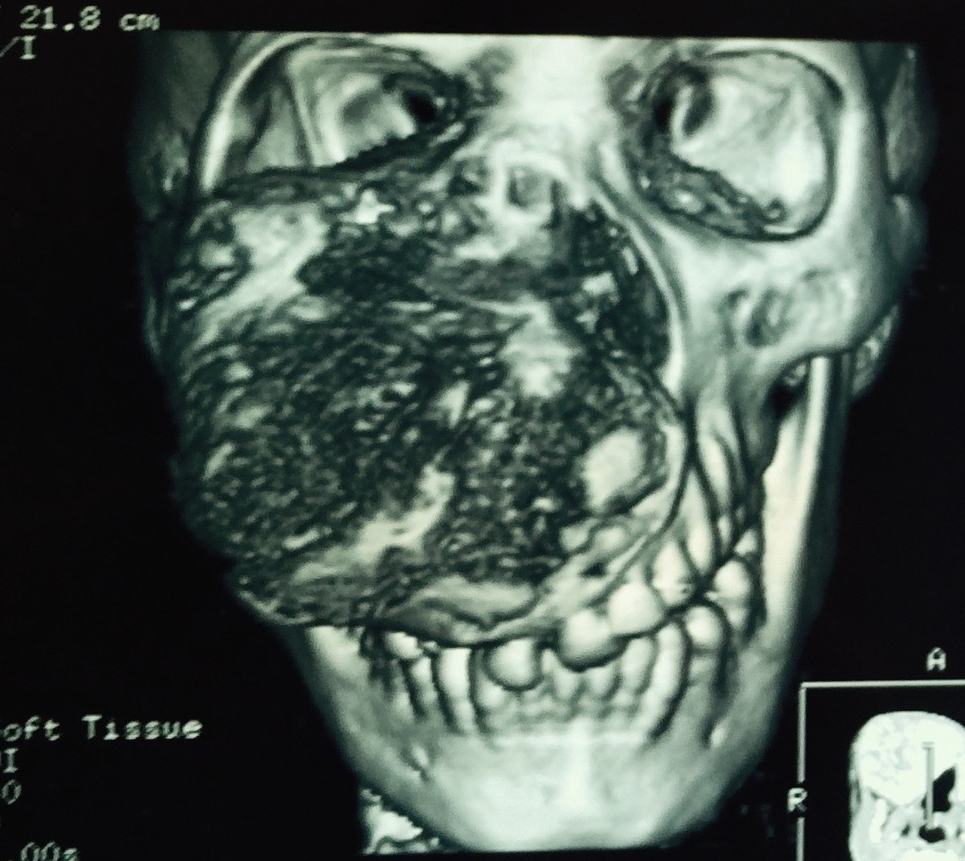

The Chief Plastic Surgeon, Andrew Hodges, has done an incredible job at developing services at the hospital under challenging circumstances and instigating the training program. One of the striking features of the visit was the extreme pathology the team encounter on a daily basis – massive facial bone tumours, extreme burns affecting not just the scalp but the skull too etc. And also notable was the prevalence of (treatable) chronic diseases (TB, malaria, HIV) that result in further chronic disability.